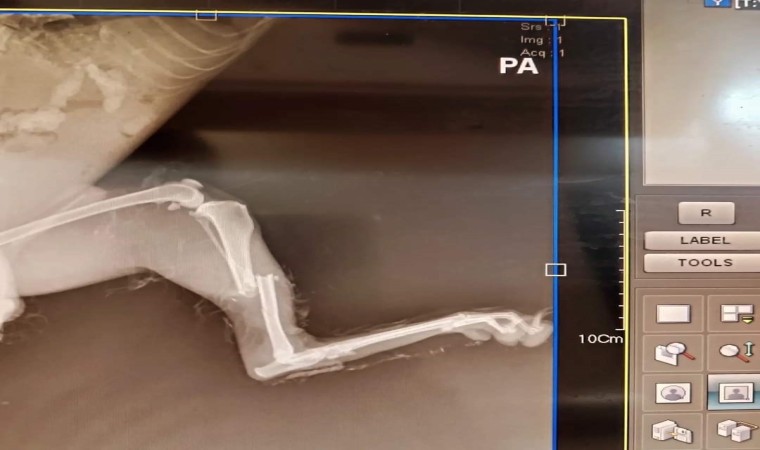

Van’ın İpekyolu ilçesinde yol kenarında duyarlı vatandaşlar tarafından yaralı olarak bulunan tilki, Doğa Koruma Milli Parklar (DKMP) Van İl Şube Müdürlüğü ekiplerine teslim edildi. Vatandaştan alınan tilki, tedavisi yapılmak üzere Van YYÜ Yaban Hayvanlarını Koruma ve Rehabilitasyon Merkezi Müdürlüğüne teslim edildi. Arka ayağı kırık olan tilki Prof. Dr. Lokman Aslan ve ekibi tarafından ameliyata alındı.

Rehabilitasyon merkezi Van Gölü havzasındaki bütün yaban hayvanlarının sorunlarıyla ilgilendiğini ifade eden merkez müdürü Prof. Dr. Lokman Aslan, "Son olarak duyarlı vatandaşlar tarafından şehir merkezinde ayağı kırık olarak bulunan tilki DKMP ekiplerine teslim edildi. Ekipler yaralı tilkiyi merkezimize getirdi. Yapılan tetkiklerde arka ayağının kırık olduğunu tespit ettik. Biz de gerekli tedavisini yaptık. Tekrardan kendi yaşam alanına bırakmak için gerekli tedavisini yapıyoruz" dedi.